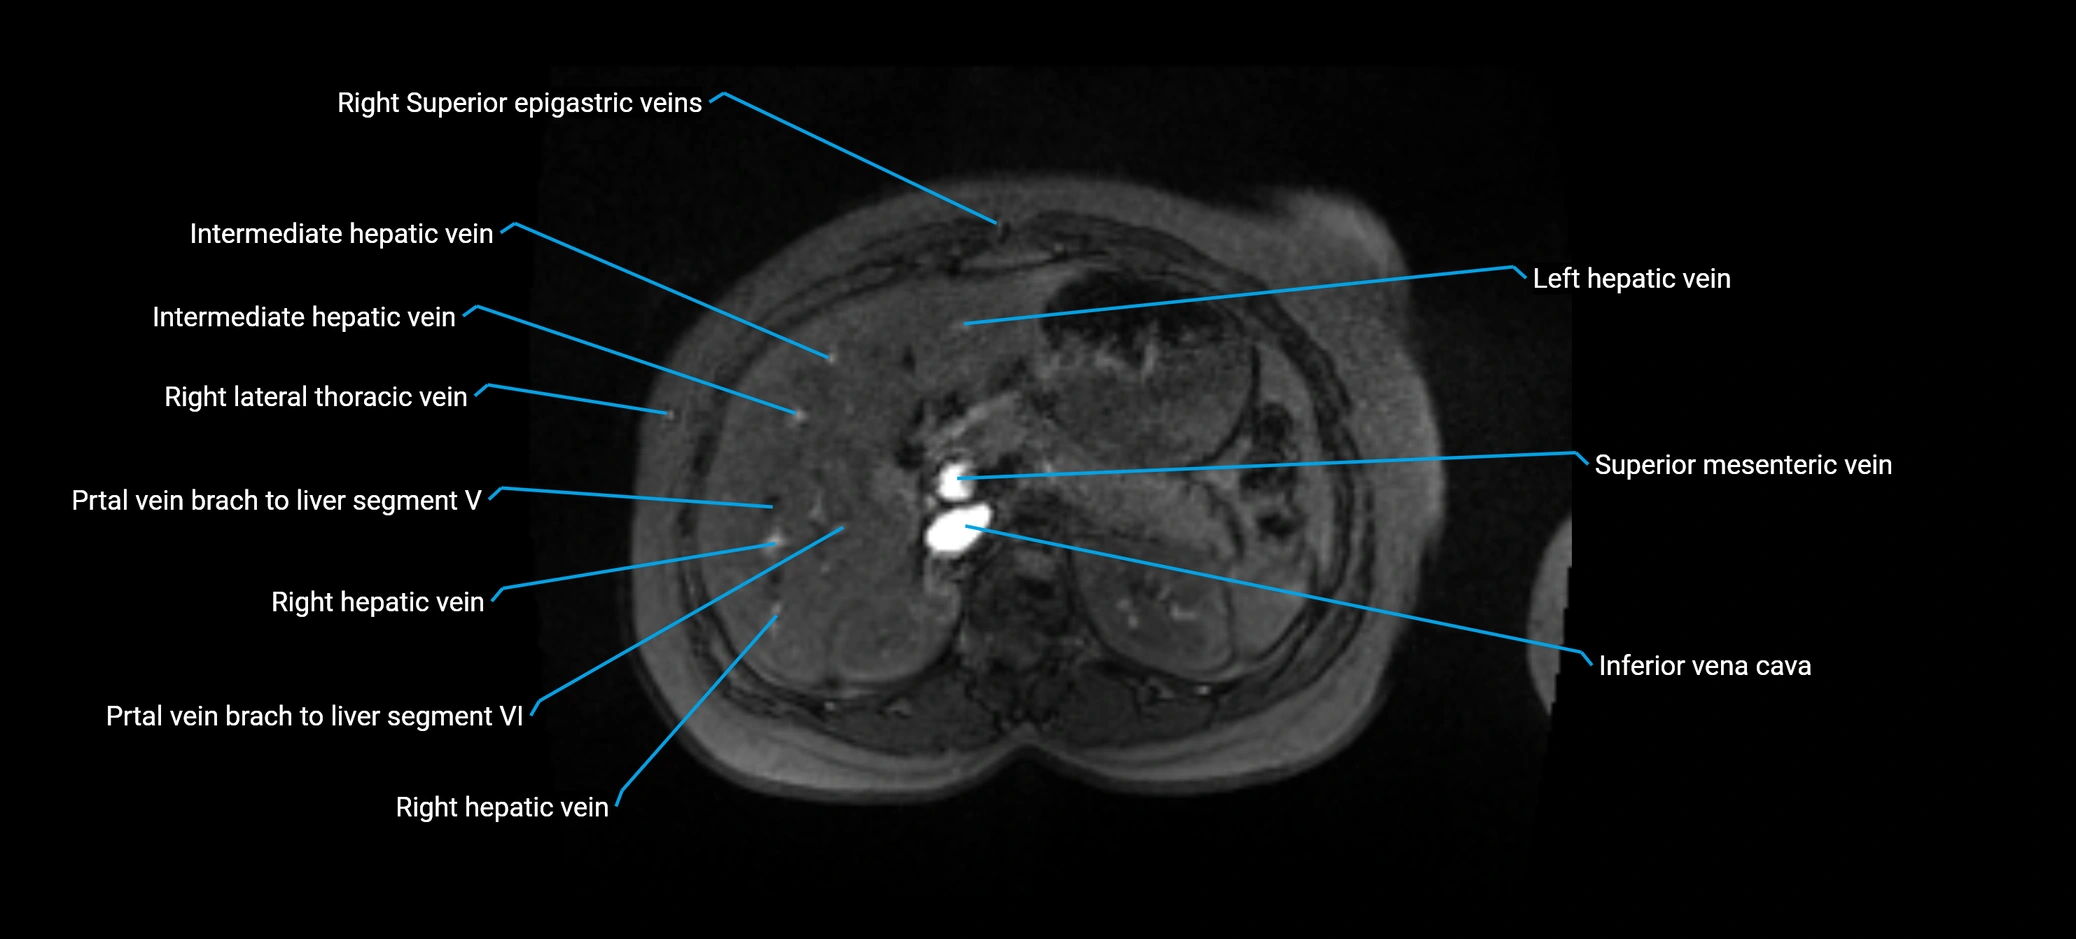

MRI image

image